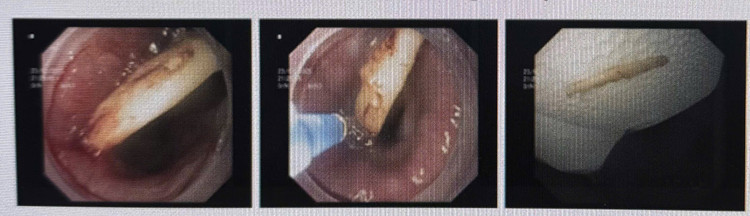

Trường hợp 2, bệnh nhân nam 76 tuổi, trong khi ăn thịt gà đã nuốt cả một mảnh “xương gà” gây cảm giác nghẹn cứng và rất chói sau xương ức.

Bác sĩ quyết định soi thực quản dạ dày cấp cứu, khi soi thấy một dị vật xương gà cắm ngang thành thực quản. Tại vị trí này, khi rút xương ra ngoài rất dễ gây thủng thực quản, đâm xuyên vào các mạch máu lớn gần tim hoặc rơi vào đường thở. Sau 35 phút chọn lựa cách gắp xoay chiều mảnh xương đã được lấy ra ngoài không gây bất cứ một tổn thương nào cho bệnh nhân.

| Dị vật được lấy ra - Ảnh BVCC |